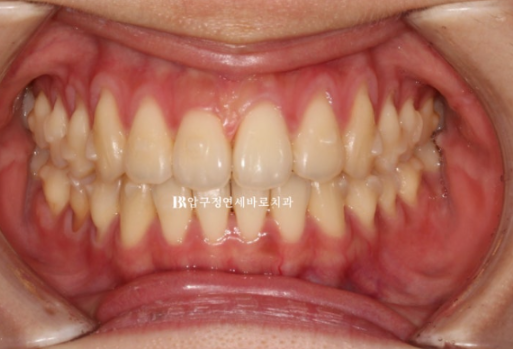

올해 2월, 앞니 덧니를 치료하고자 오신 환자분입니다.

앞에서 보면 별 문제가 없어보이지만,

앞니 두개가 튀어나온 토끼이빨이며 특히 우측 앞니가 많이 들려있습니다.

어금니 교합은 좋은 상태라서 인비절라인 익스프레스를 권유드렸습니다.